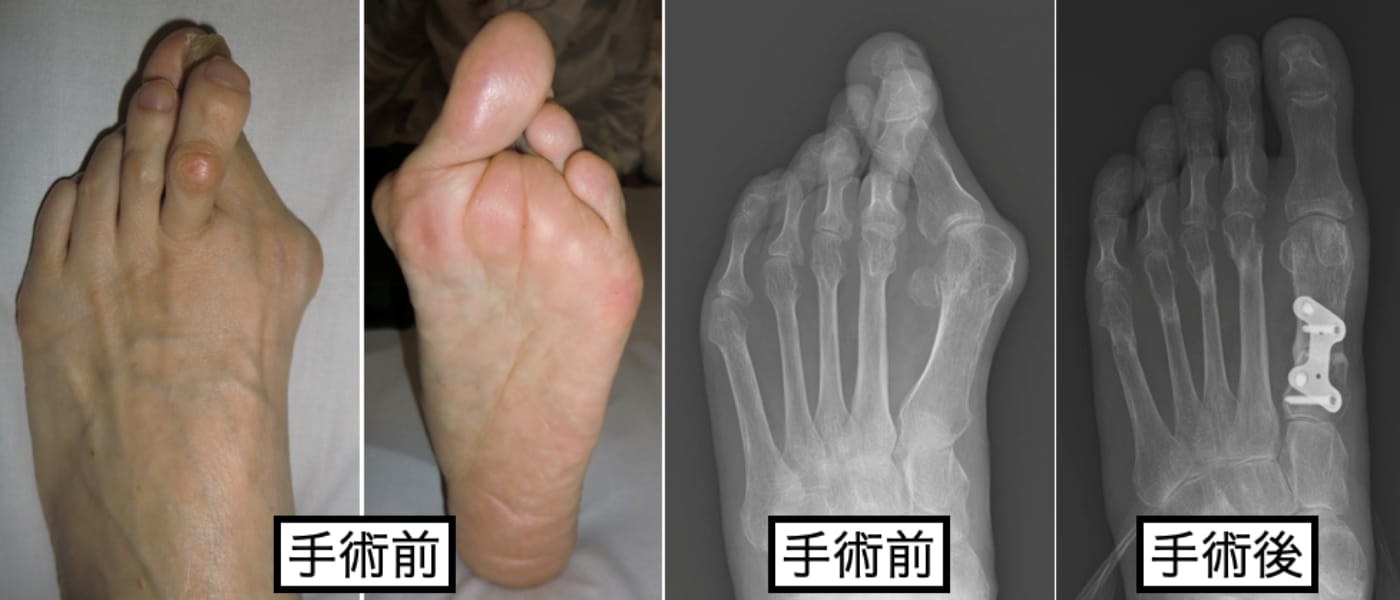

関節リウマチによる足部変形

当科では、関節リウマチによる前足部変形に対して、従来行われていた第1MTP関節固定術と第2〜5中足骨頭切除による切除関節形成術を組み合わせた足趾形成術も行なっております(下図)が

抗リウマチ治療により、疾患活動性が落ち着いている場合や足趾関節の破壊が高度でなければ、可能な限り関節温存型の足趾形成術を行なっています(下図)。

足趾関節を温存することで、足部の踏み返し運動の改善が期待できるため、歩容の改善も期待できます。また、中足骨頭を残す際に骨頭の配列も矯正するため、足底部の有痛性胼胝の自然軽快も期待できます(下図)。